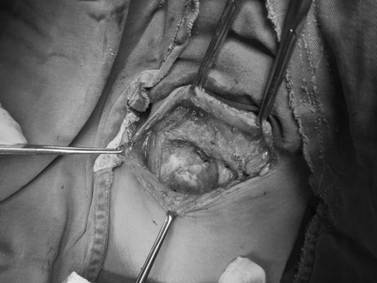

▲术中照片

从一开始就注定这是一个曲折的故事。打开伤口后(图1),真相并非医生们术前想象,当王兵教授一层一层小心取出伤口内压迫纱布后(图2),突然一股鲜血喷涌而出,“是动脉出血”!王教授第一时间做出判断,并同时再次用纱布填塞止血。与死神搏斗,犹如与高手过招,胜负就在一瞬之间,而取胜之关键就在于术前是否有充分的预判,和针对突发情况的预案。

▲ 图1